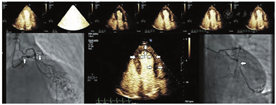

虽然在2008年的ASE专家共识声明中就已经提到了VLMI多脉冲序列方案在多数系统上都可用[1],但最近才有制造商开始将它们用于LVO。VLMI技术最初是为心肌灌注评估而设计的,但它们对于微泡检测的敏感性和无漩涡伪影的心尖部心腔的完整造影显示对负荷LVO成像有很大的帮助。多中心和前瞻性单中心研究均证实了VLMI成像可以有效地检出RWM异常[16,45,66]。除了增强敏感性和心尖部的勾勒之外,VLMI技术还可检测负荷试验时透壁室壁增厚无法检出异常的心内膜下室壁增厚异常情况[42,66]。结合LVO以及高机械指数脉冲破坏后的心外膜层再充填过程有助于勾勒心内膜边缘和分析该处室壁增厚(图5和视频7;在www.onlinejase.com获取)。将UEA与VLMI成像用于室壁增厚和缺血的评估,并结合多巴酚丁胺负荷超声心动图对左束支传导阻滞患者进行常规评估,被证明可提高CAD的检出,并可独立预测死亡率和心血管事件[67]。

很明显,这些研究基础显示UEA提高了静息和负荷成像过程中RWM分析的诊断准确性。VLMI成像对于RWM分析来说似乎是最佳的,原因在于灌注数据带来的增量价值,有助于区分因心内膜下缺血引起的轻微的室壁增厚异常。这似乎对所有冠脉支配区域都有帮助,尤其是通常难以显影的节段(图6,视频4和7;在www.onlinejase.com获取)。由于冠脉支配区域的疾病可能只影响心尖或胸骨旁切面的某个特定节段,因此当任何节段无法充分可视化时,写作组建议应用UEA进行LVO检查。